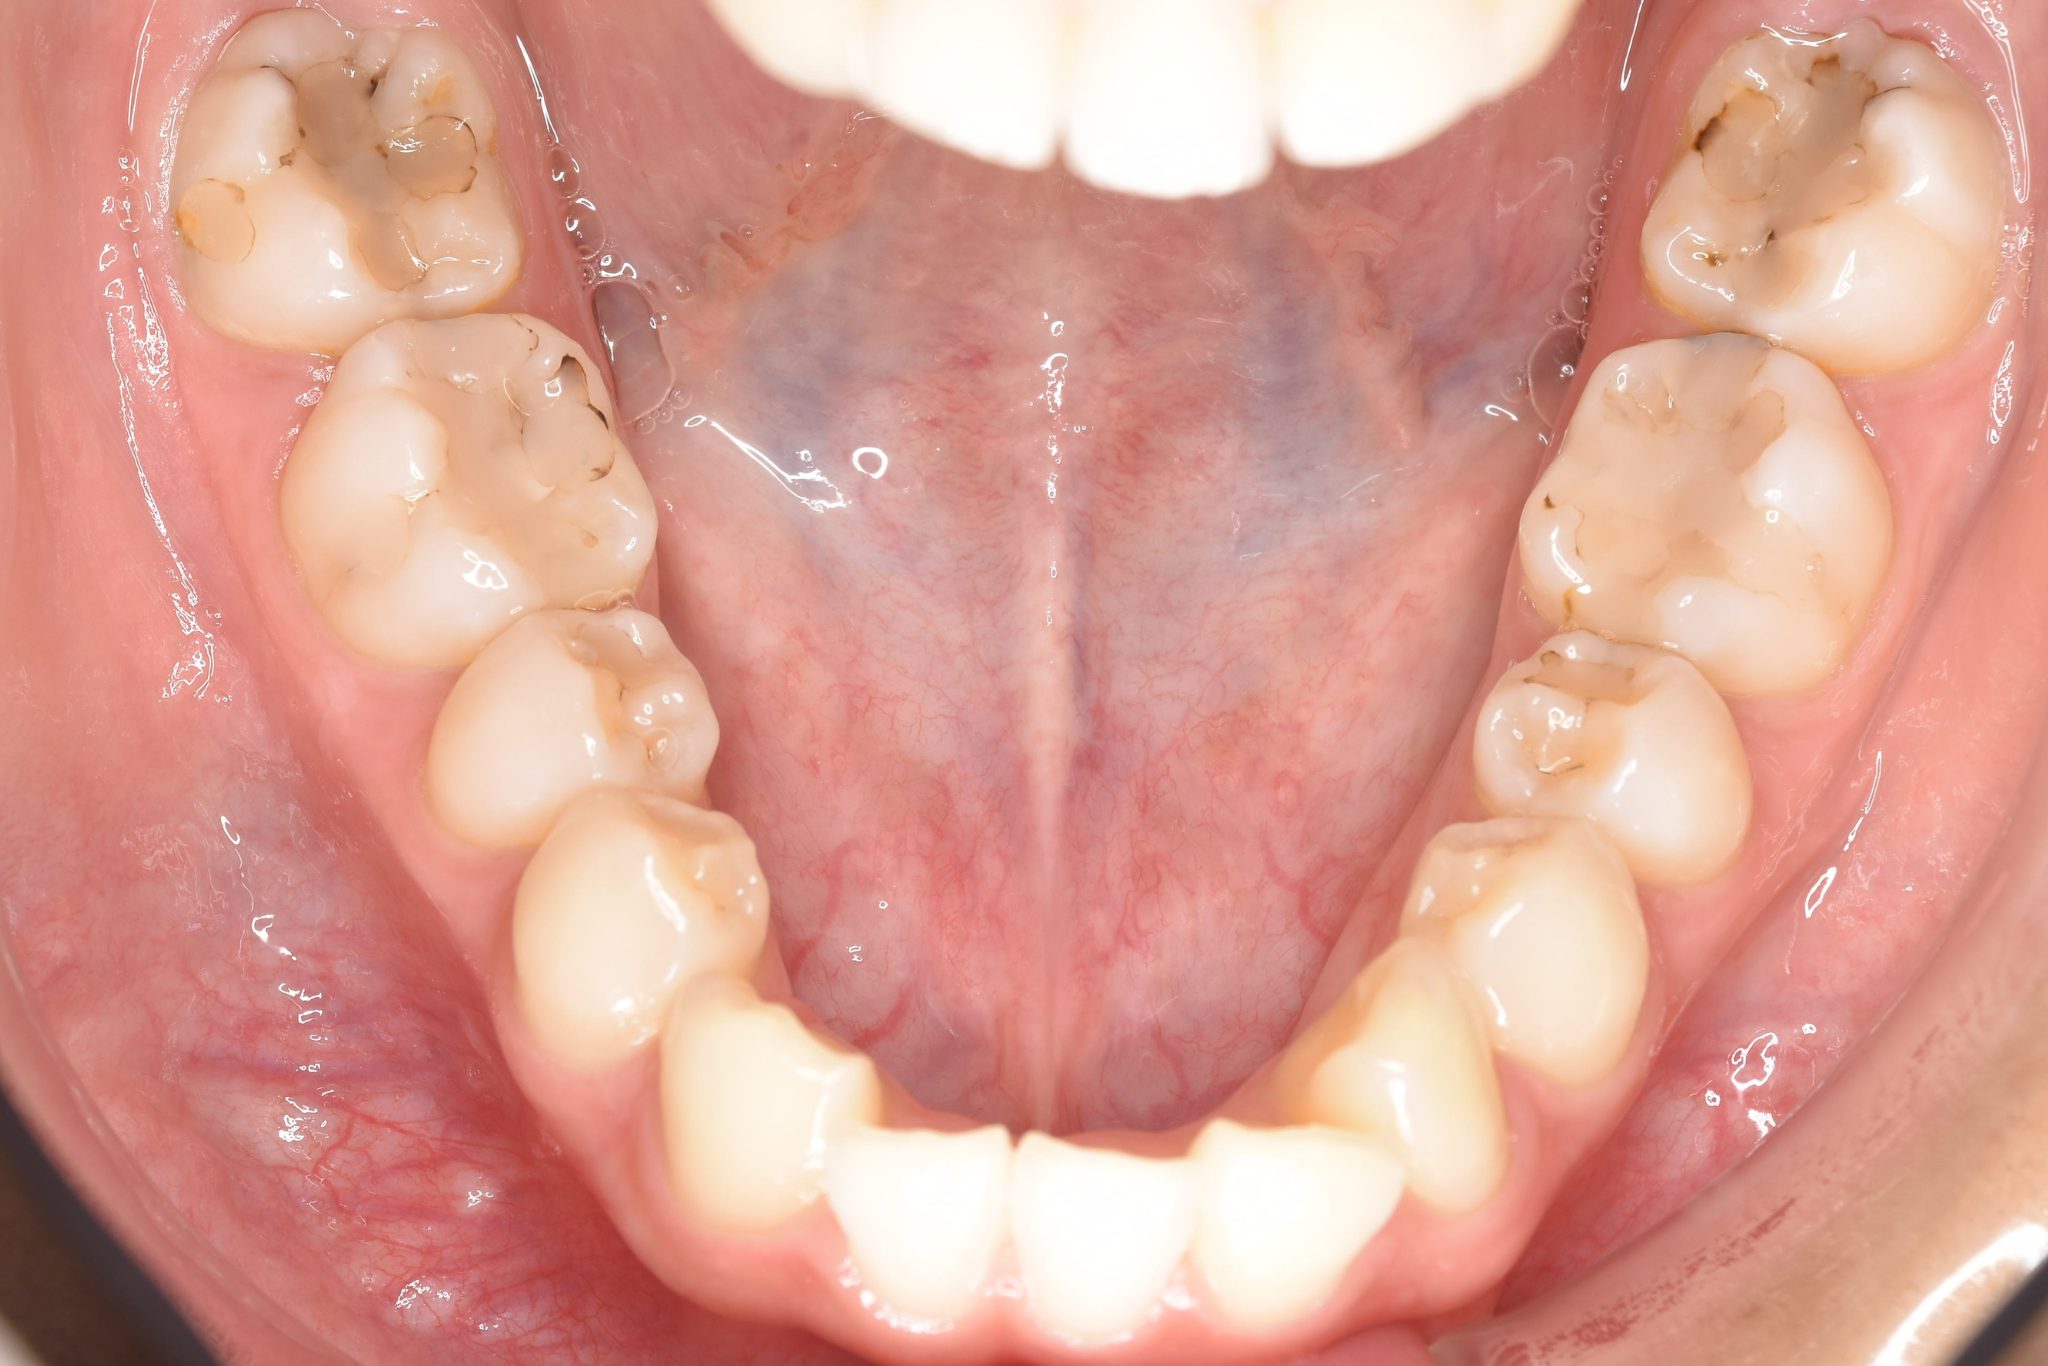

ビフォー

ワイヤー矯正治療|症例_009

主訴 出っ歯

施術内容 MSEと下顎リンガルアーチを用いて上下顎骨を拡大した。

その後マルチブラケット装置とミニインプラントを用いて非抜歯で歯牙を配列した。

下顎前歯が1本先天性欠損であったが、良好な咬合を獲得した。口元の突出感と鼻閉症状は改善された。

治癒期間 2年3ヶ月間